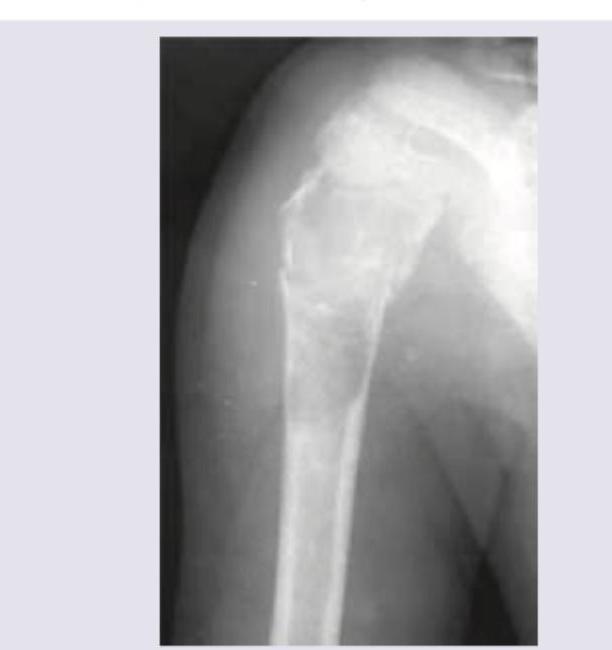

Question 10: Comment on the diagnosis of the presentation shown below:

- A. Unicameral bone cyst (Correct Answer)

- B. Aneurysmal bone cyst

- C. Osteoblastoma

- D. Osteoclastoma

Explanation: ***Unicameral bone cyst*** - This X-ray shows a **well-defined, lytic lesion** in the proximal humerus, consistent with a unicameral bone cyst, often presenting in the **metaphysis** of long bones in children and adolescents. - The lesion has a **thin, sclerotic rim** and shows **no significant periosteal reaction** or soft tissue mass, which are classic features. *Aneurysmal bone cyst* - While also a lytic lesion, an aneurysmal bone cyst typically appears more **expansile** and **multiloculated**, often with a **"soap bubble" appearance**. - It usually has a **thicker, more irregular rim** and can present with faster growth or more aggressive features than a unicameral bone cyst. *Osteoblastoma* - Osteoblastomas are typically **osteoblastic (bone-forming)** tumors, which would appear more **sclerotic** or mixed lytic-sclerotic on X-ray, rather than a purely lytic lesion like the one shown. - They commonly affect the **spine or long bones**, but their radiographic appearance of predominant bone formation is not seen here. *Osteoclastoma* - Osteoclastomas, also known as **giant cell tumors of bone**, are usually found in the **epiphysis** of long bones in mature skeletons, which is a different location than observed. - They are typically **aggressive lytic lesions** with poorly defined margins and can extend to the articular surface, which is not characteristic of the well-demarcated lesion in the image.